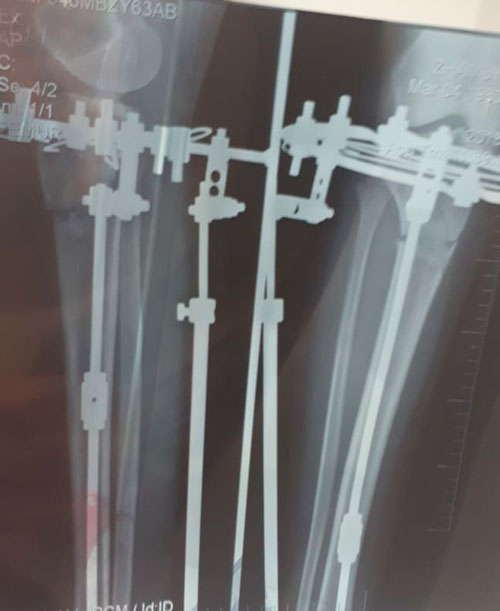

Исходник - 38 лет. Астана.

Дата операции 31.05.2018г.